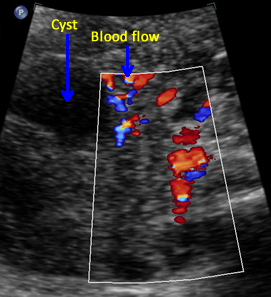

Above. Ovarian cyst. Case 1. 35 weeks gestation. The cystic structure arises in the lower abdomen and is adjacent to the anterior abdominal wall just to the left of mid-line. The cyst measures 45 mm x 36 mm meeting critical cutoff values which increase the risk for torsion and/or infarction.

Above. Ovarian cyst. Case 1. 35 weeks gestation. Blood flow to the cyst is confirmed.